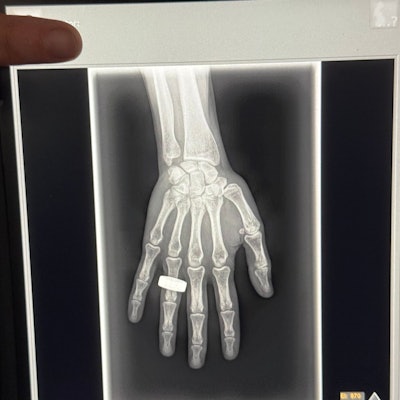

The commander of the Fram2 space mission has posted on social media what may be the first x-ray image taken in space.

In a post on the social media platform X on 1 April, Chun Wu wrote that on the second morning of the flight, the crew woke up, had breakfast, and “took a few x-ray images.”

Image from an X post by @satofishi.

The post has received over 14.9 million views at the time of writing. The image appears to be a nod to the first x-ray ever taken by Wilhelm Roentgen of his wife Anna Bertha Ludwig's hand on 22 December 1895.

The Fram2 mission launched on 31 March and is expected to be in orbit for at least another day. The crew is conducting more than 20 science experiments, including taking images of each other with an ultraportable x-ray machine.